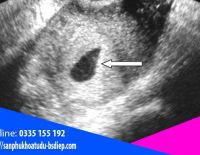

Giải đáp: Mang thai ngoài tử cung siêu âm có thấy không?

Mang thai ngoài tử cung siêu âm có thấy không được nhiều chị em quan tâm nhằm sớm chủ động xử lý. Bởi đây là một dạng thụ thai không bình thường và gây nguy hiểm đến sức khỏe người mẹ....